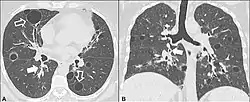

Advanced centrilobular emphysema showing total lobule involvement on the left side.

Centrilobular emphysema also called centriacinar emphysema, affects the centrilobular portion of the lung, the area around the terminal bronchiole, and the first respiratory bronchiole, and can be seen on imaging as an area around the tip of the visible pulmonary artery. Centrilobular emphysema is the most common type usually associated with smoking, and with chronic bronchitis.[11] The disease progresses from the centrilobular portion, leaving the lung parenchyma in the surrounding (perilobular) region preserved.[10] Usually the upper lobes of the lungs are affected.[11]